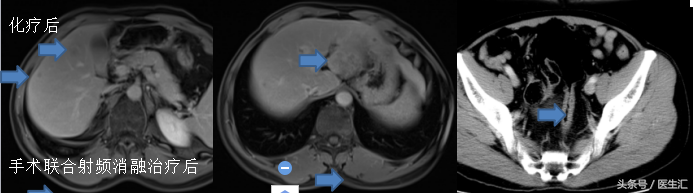

化疗后

手术联合射频消融后

乙状结肠溃疡型高分化腺癌,肿瘤大小:2.5*37.5px。浸润至浆膜下,侵犯神经。切缘阴性。淋巴结:见癌转移(3+/12)另见癌结节2枚。

“左肝外叶”切除标本大小16*8*112.5px,剖面见一肿块,大小3.2*55.00000000000001px,另见一灰白结节,大小0.9*17.5px,镜示高分化腺癌,肝脏切缘阴性。